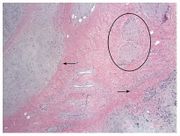

| 16:45, 12 November 2022 | Pleomorphic adenoma 3.jpeg (file) |  |

53 KB | 1 | |

| 16:44, 12 November 2022 | Pleomorphic adenoma 2.jpeg (file) |  |

76 KB | 1 | |

| 16:44, 12 November 2022 | Pleomorfic adenoma 1.jpeg (file) |  |

74 KB | 1 | |